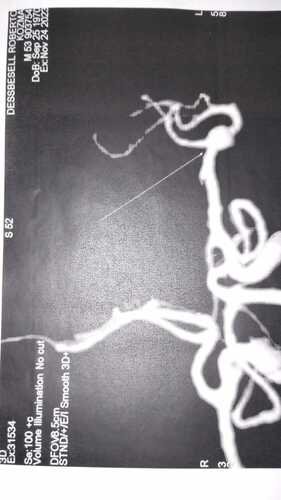

Eu Roberto Dessbesell 53 anos , motorista (caminheiro) na madrugada do dia 27 de julho de 2023 tive um AVC enquanto trabalhava (estava em viagem há Pelotas ) . Fui socorrido pelo atendimento médico do pedágio que me deu os primeiros socorros, fui levado para o hospital inconsciente e lá fiquei internado por 2 dias até que fui transferido ao Hospital de Panambi desde então estou em tratamento com neurologista e fisioterapia . Desde o AVC estou impossibilitado a trabalhar e fazer qualquer tipo de esforço físico pq esse aneurisma pode estourar a qualquer momento . Não podemos esperar pelo SUS pq o tempo para ser chamado é uma média inicial de 3 anos pra mais . E eu preciso fazer a cirurgia o mais rápido possível .

Recentemente tive que fazer novos exames e foi constato que preciso urgentemente fazer uma micro cirurgia na cabeça para retirada de um coágulo que se formou decorrente ao AVC.